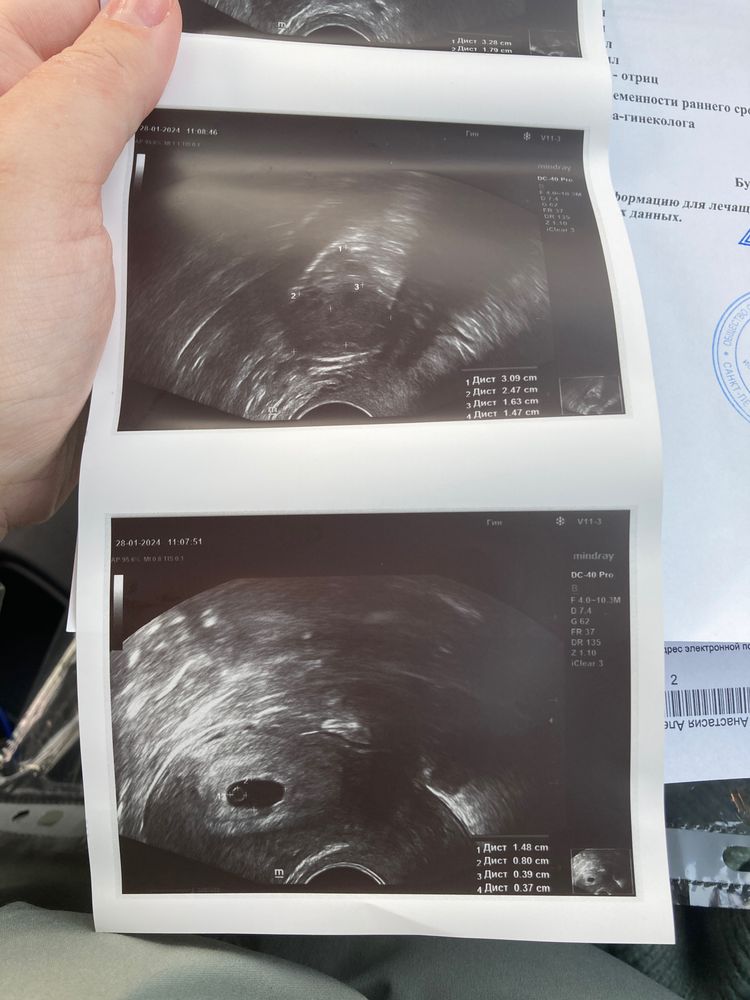

Сходила на узи, врач сказала, что то, что видно - слишком маленькое для срока и ничего не ясно. Посмотрите, пожалуйста, заключение. Срок 6+0

Ничего страшного, срок еще небольшой. Главное, что эмбрион есть, желточный мешок визуализируется.

КТР 3,9 мм (0,39 см) соответствует акушерскому сроку (по месячным) 6 недель, нормально у вас все (в заключении похоже эмбриональный срок, он ровно на 2 недели меньше акушерского)

Ваш ктр это 6 недель . Обычно можно увидеть уже сб , но узисты и аппараты разные . Должны были сильнее приблизить и посмотреть пульсацию .по идее эмбрион размером с жм должен быть, но на этом снимке почему то его не видно

Кажется, жм и эмбрион у меня на разных снимках, 4 и 1 соответственно. Врач много говорила про несоответствие срокам, я перепугалась и даже не подумала попросить посмотреть сб тщательнее…

Ктр у вас по сроку,3,9 мм это 6 недель акушерских, единственное что сб нет,но может аппарат не очень,в заключении не акушерский срок